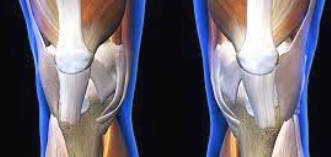

3단계: 심각한 연골 손상 증상

연골 손상이 심각한 단계에 이르면 일상생활에 심각한 지장을 초래합니다. 평지 보행에서도 통증이 발생하며, 무릎을 움직일 때마다 심한 통증과 함께 관절음이 지속적으로 나타납니다.

무릎 관절의 변형이 육안으로도 확인되며, 무릎이 완전히 펴지지 않거나 구부러지지 않는 관절 강직이 나타납니다. 무릎에 힘이 빠지는 느낌과 함께 관절 불안정성이 심화되어 넘어질 위험이 증가합니다.